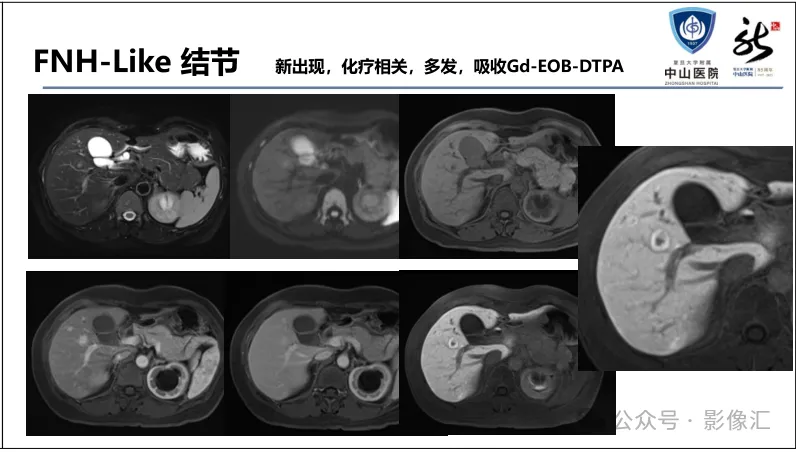

>【精品课件】如何正确判读肝胆特异性对比剂增强图像?

肝胆特异性对比剂增强肝胆图像判读方法与策略,课件来源于网络,作者复旦大学附属中山医院放射科饶圣祥教授。